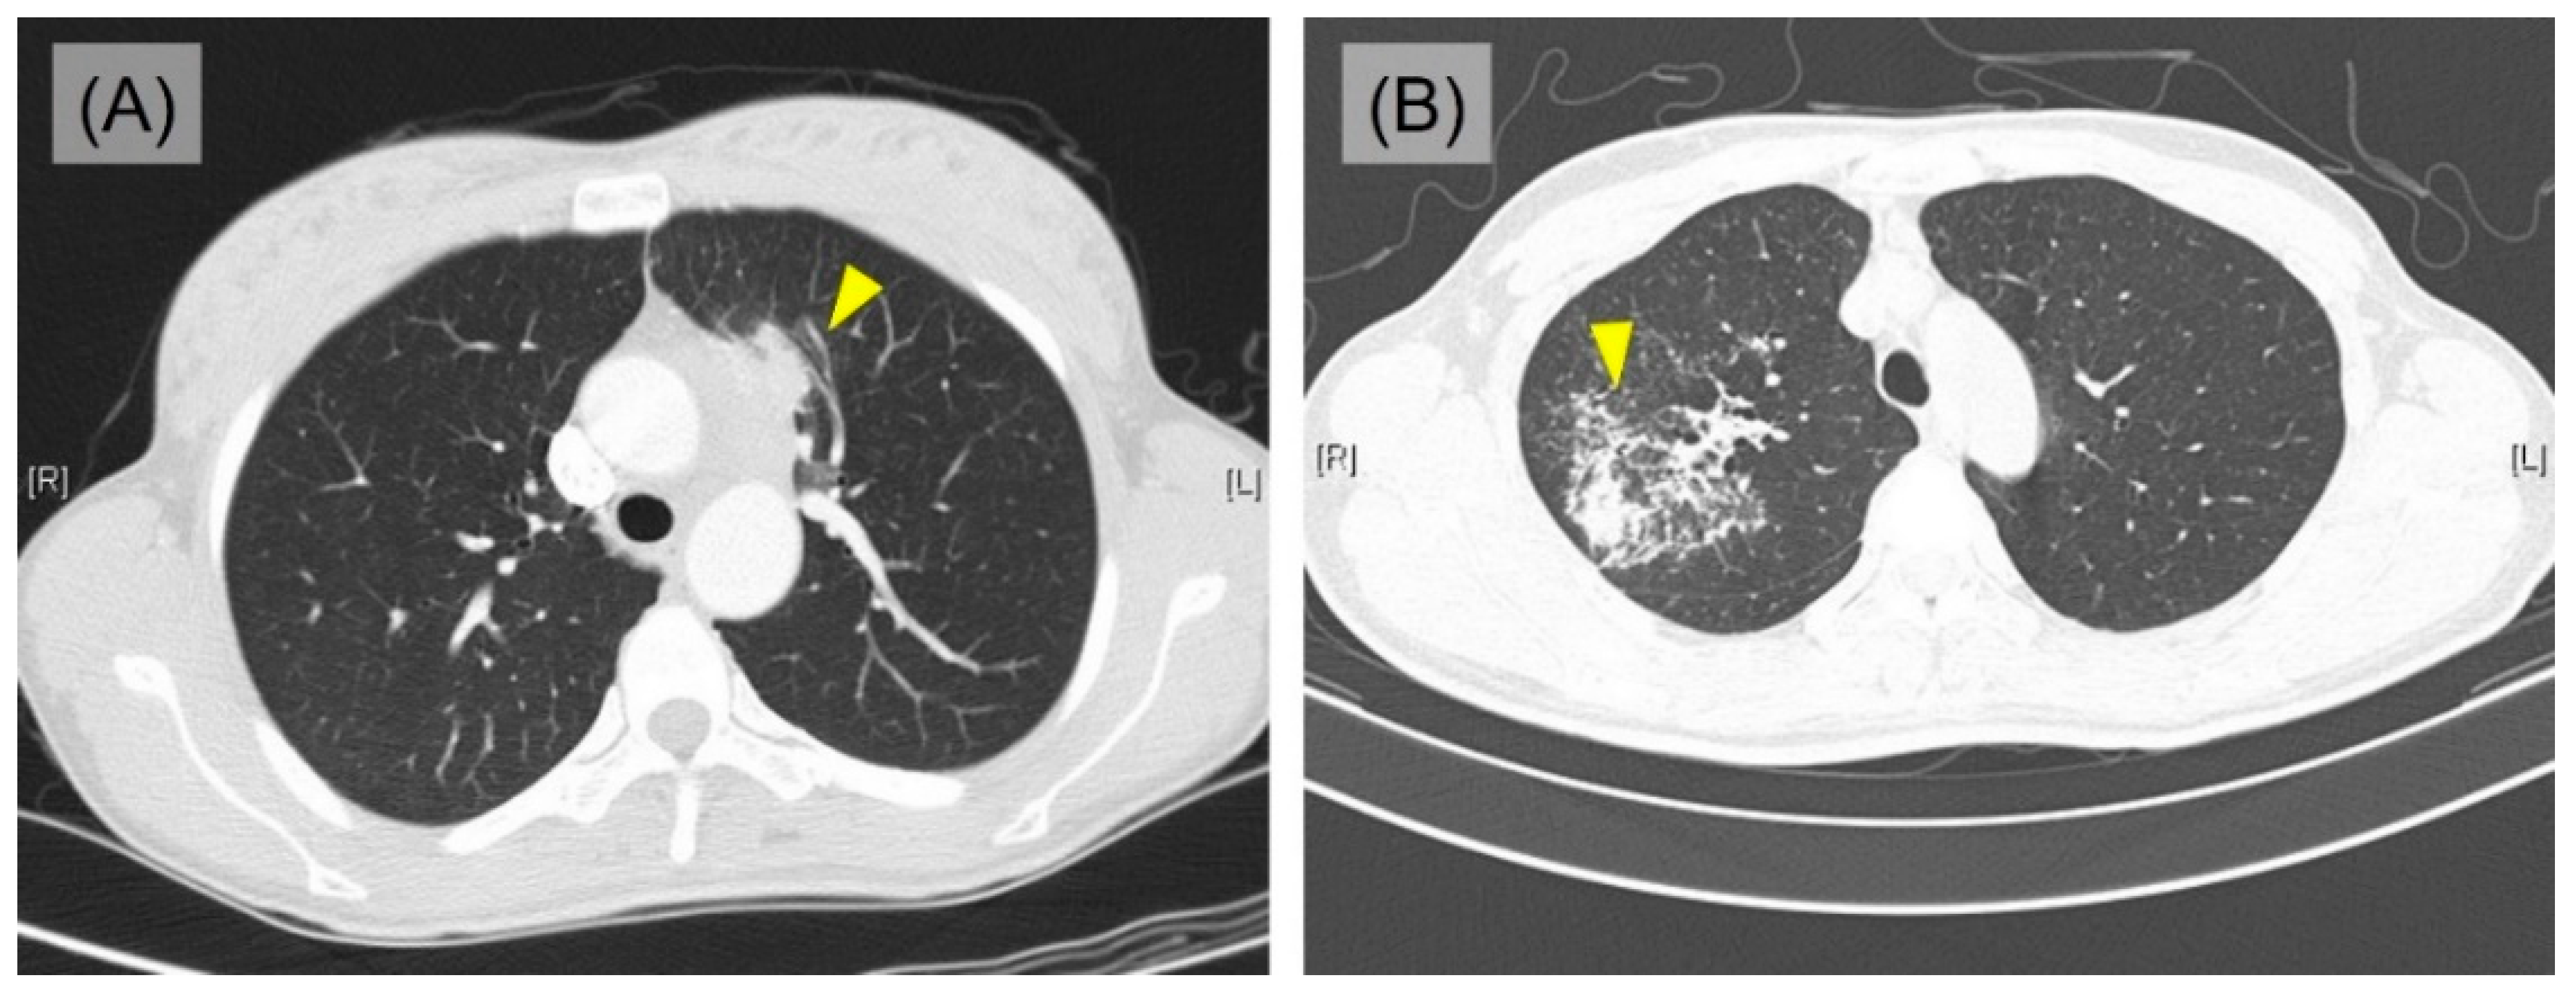

The clinical data of the 10 PPHL cases are summarized in Table 1. Detailed clinicopathological characteristics are listed in Supplementary Table S1. The median observation period was 4.5 years (range, from 1 month to 21 years). The median age of patients at diagnosis was 41 years (range, from 27 to 72 years), and female predilection was identified (female: male = 6:4). Three patients had a history of smoking (range, 1 to 40 pack years). Seven patients complained of localized and/or generalized symptoms; cough, sputum, chest discomfort/pain, and weight loss, but the rest of 3 patients were asymptomatic. In the initial chest computed tomography (CT), 8 patients presented pulmonary mass (size range, from 4.1 to 10.5 cm) accompanying enlarged mediastinal lymph nodes, which highly indicated primary lung cancer (Figure 1A). Two patients showed consolidation, which suggests the possibility of tuberculosis or nontuberculous mycobacterial infection (Figure 1B) and pneumonia. Most of the masses and consolidative lesions were located in upper portion of the lung (5 in left upper lobe and 4 in right upper lobe), except one which was identified in left lower lobe. The bronchoscope examination was performed on 8 patients and most of them had no specific findings except 2 cases showing equivocal narrowing and a suspicious mucosal nodular infiltrating lesion, each.

Figure 1.

Imaging findings of PPHL. (A) Single mass (yellow arrowhead; case 4). (B) Consolidation (yellow arrowhead; case 9).